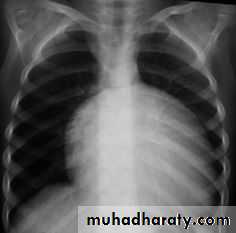

CXR shows cardiomegaly with decreased pulmonary blood flow

CXR shows cardiomegaly